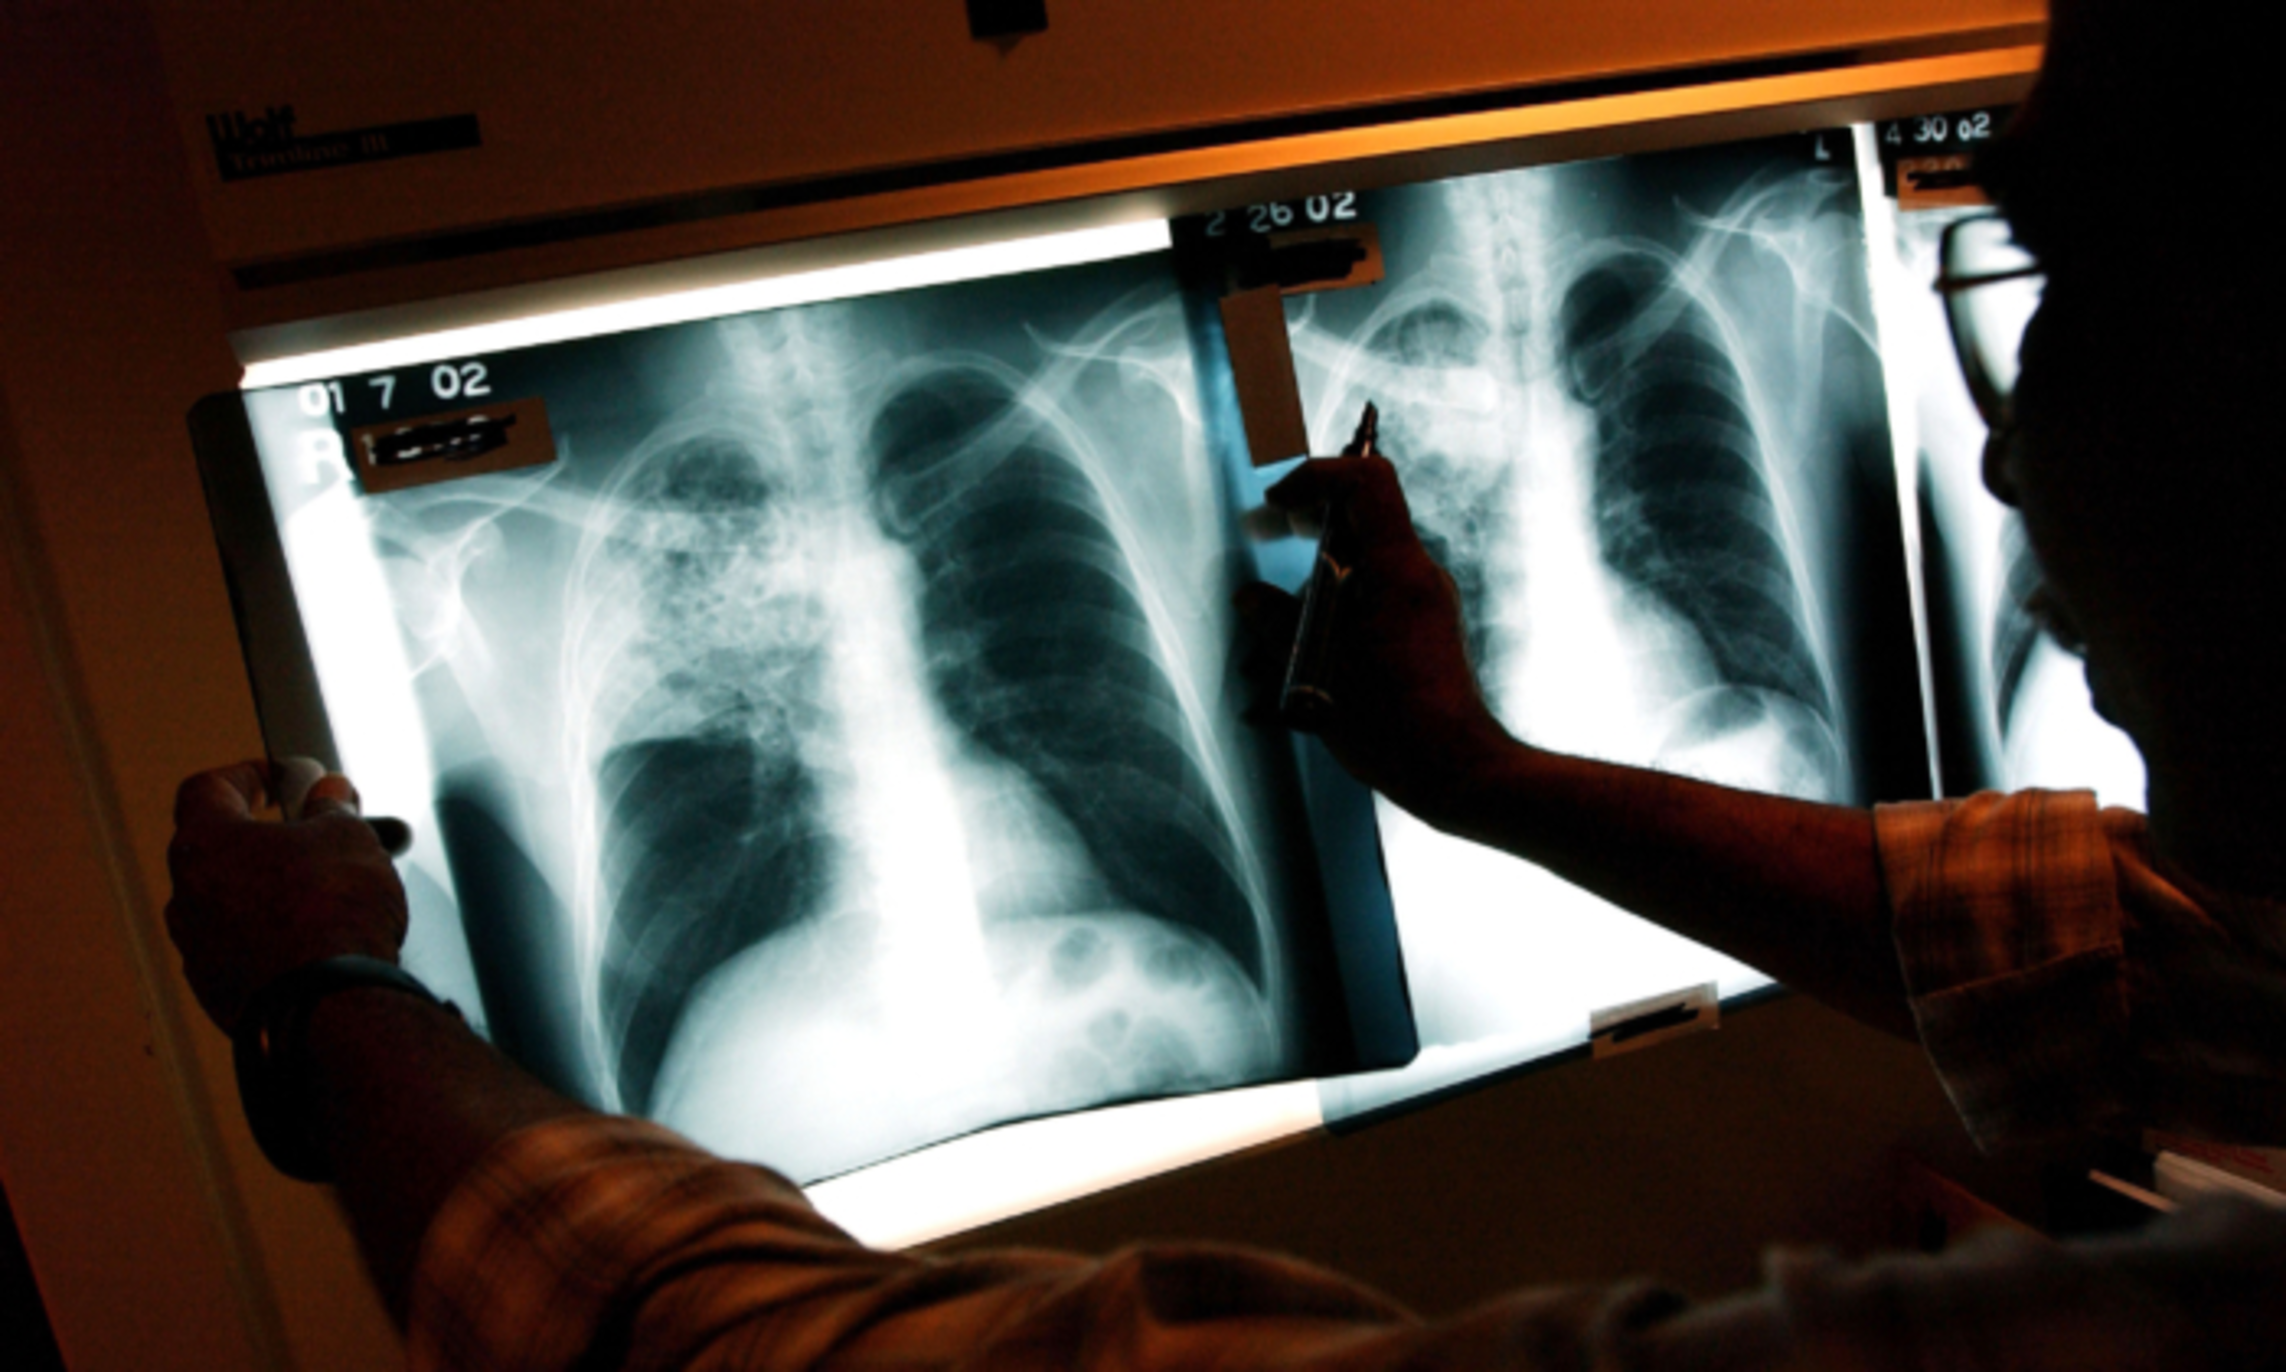

California Agency Issues ‘Health Advisory’ on Tuberculosis

Officials in California recently issued a “health advisory” after a “substantial increase” in the number of cases of the deadly bacterial infection. The state reported around 2,100 cases of active tuberculosis, or TB, last year, or a 15 percent jump from the previous year, officials said in a recent report. Many of the cases involved are people with latent infections that later became active, which allowed them to develop symptoms and spread it to other people, according to the California Department of Public Health. As a result, the agency in late March sent out a “health advisory” to health care providers across the state to be aware of the increase in cases, adding they should consider tuberculosis in the “differential diagnosis of community acquired pneumonia or other respiratory illnesses, particularly among patients with a risk factor for TB or with prolonged symptoms.”...